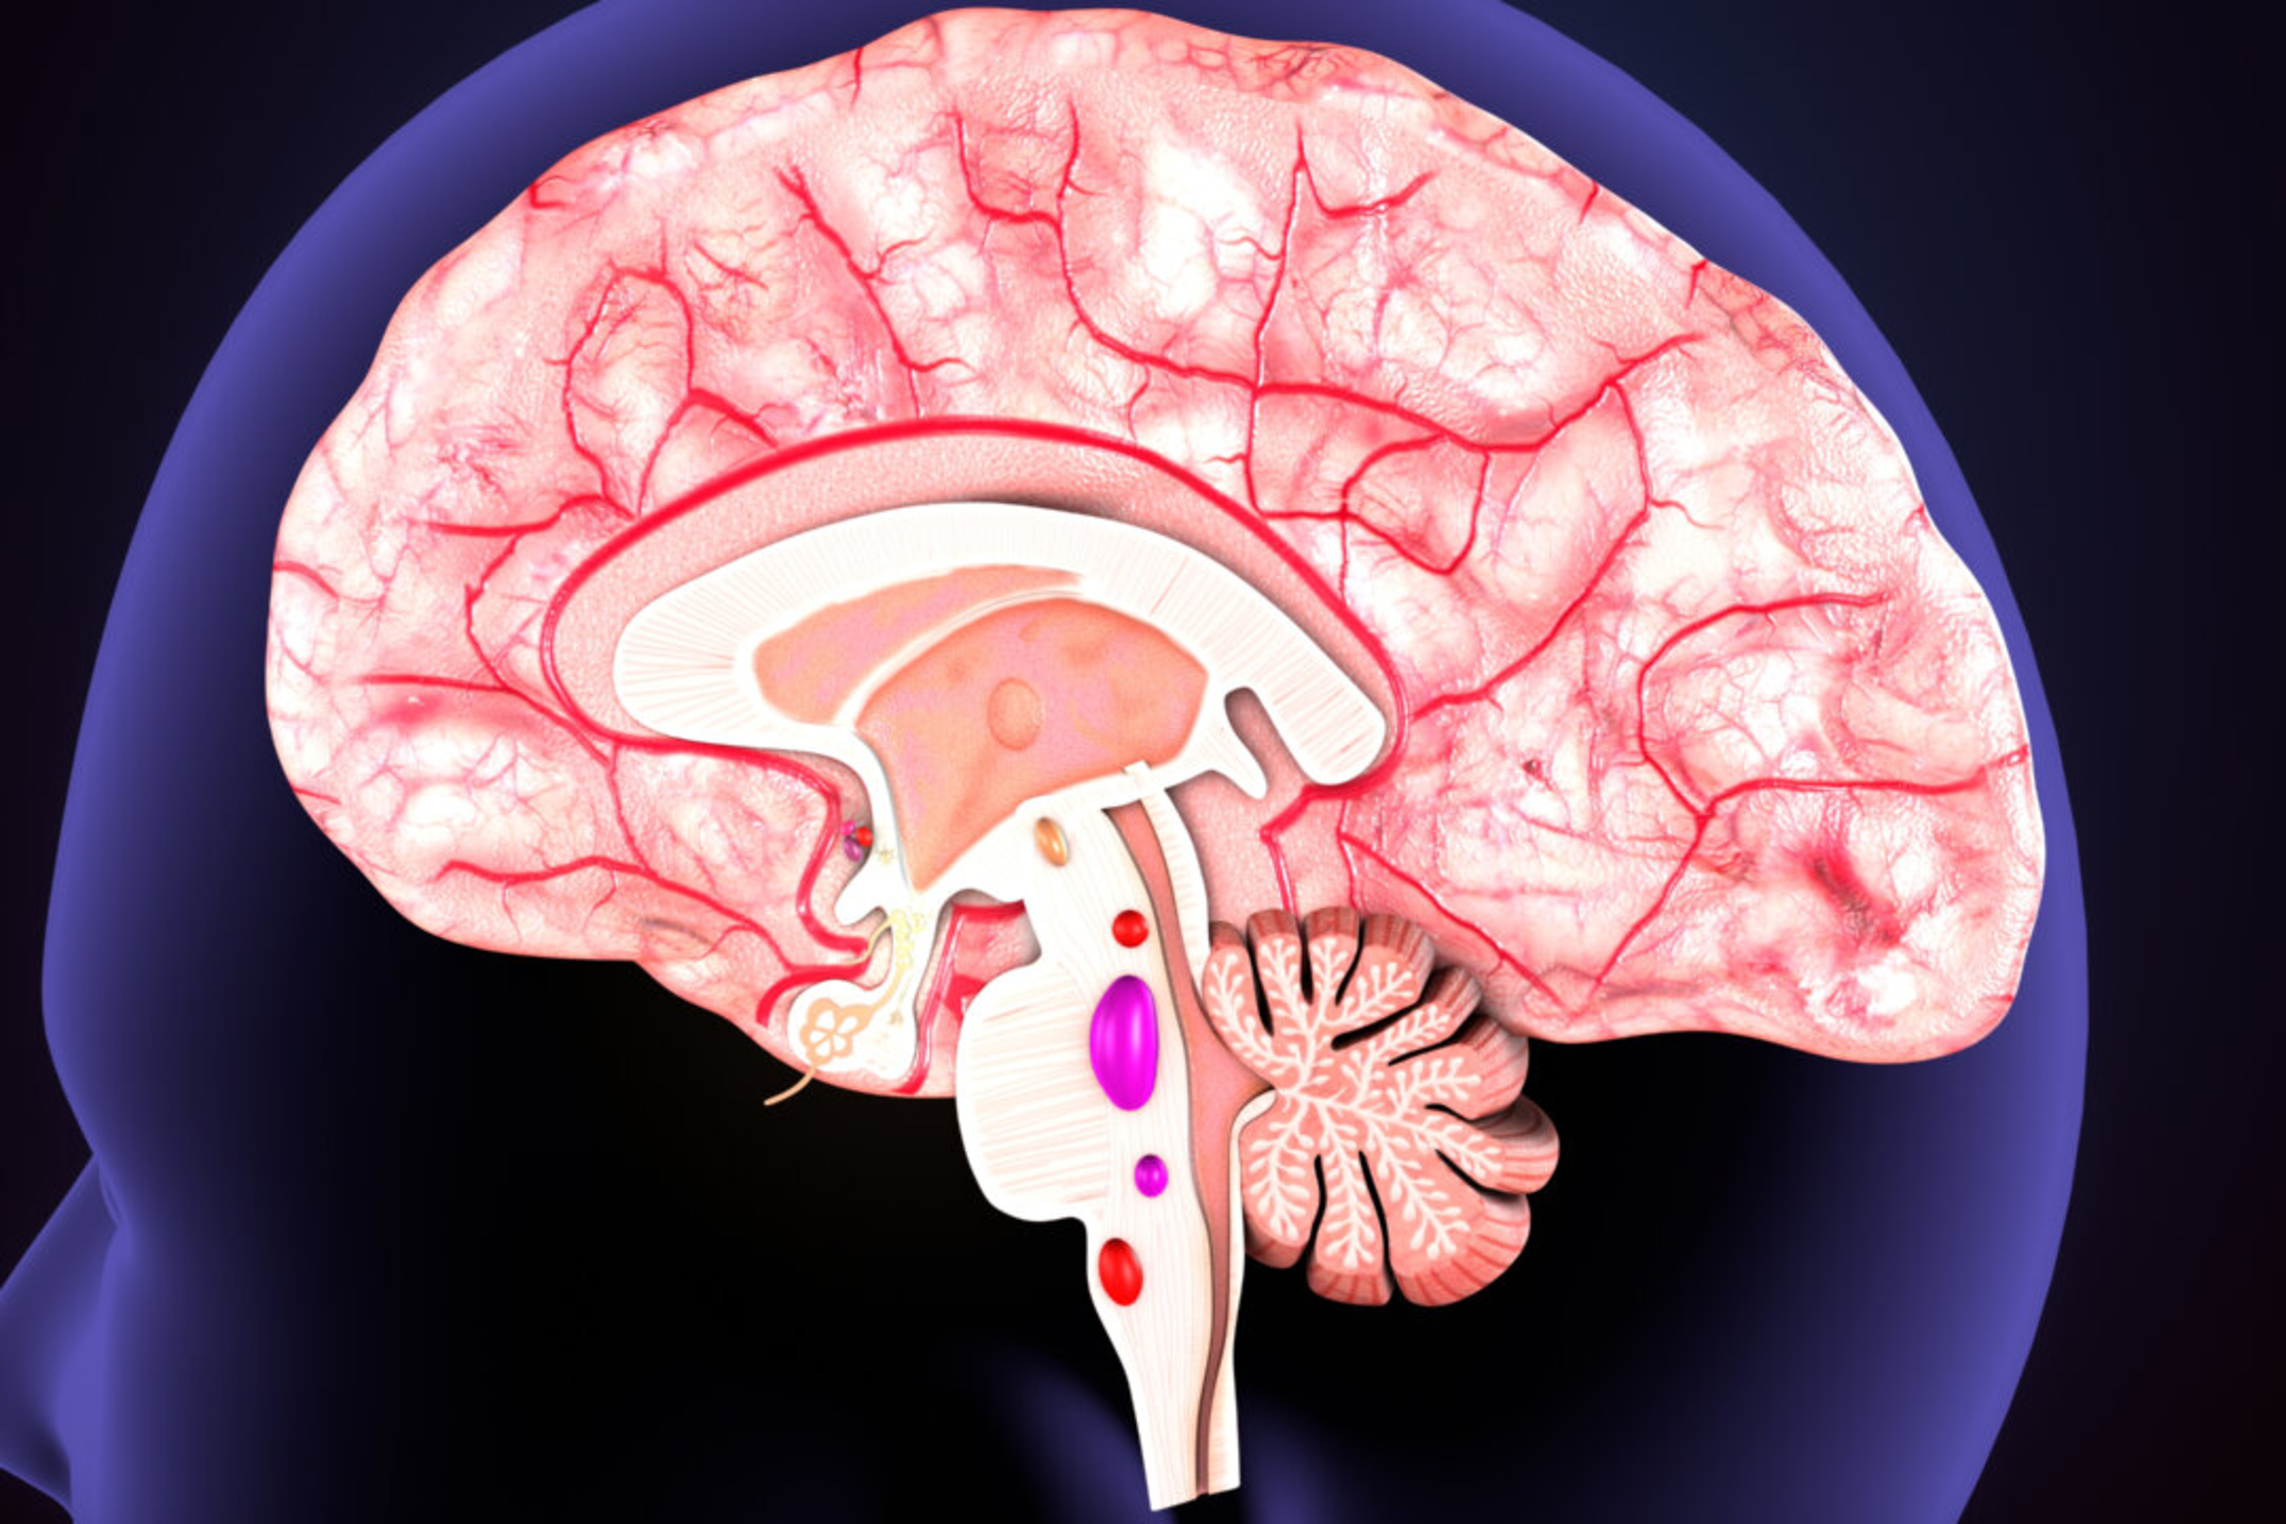

Scientists Uncover the Clue to Memory Formation

Researchers from the University of Queensland’s Brain Institute have revealed the mechanism by which memories are formed and consolidated, with the peer-reviewed study recently published in the European Molecular Biology Organization Journal. Lead researcher Isaac Akefe said this breakthrough holds promise for potential treatments targeting neurodegenerative conditions such as dementia and Alzheimer’s disease. “We’ve shown previously that levels of saturated fatty acids increase in the brain during neuronal communication, but we didn’t know what was causing these changes,” Mr. Akefe said, about a study published in Nature Communications Journal in June 2021. “Now for the first time, we’ve identified alterations in the brain’s fatty acid landscape when the neurons encode a memory....